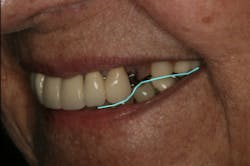

Figure 12 illustrates the horizontal position of the maxillary anterior teeth to the lower lip. The goal of this photo is to see the incisal edge just inside the lower lip line. (3) With this patient, it was clear that the horizontal position was placed too far facially.

At rest or repose, ideally 1 mm to 3 mm of incisal edge is revealed. Often, aging causes the upper lip to drop, which reveals less than the 1 mm to 3 mm of incisal edge. (4) This patient does show some reveal, as illustrated in Figure 13, but at her age, none is expected to be seen. However, to confirm this, the “E” smile photo was used. This photo illustrates where the incisal edge falls between the upper and lower lips. Figure 14 illustrates how to use this photograph to help determine the vertical position of the incisal edge. Ideally, the incisal edge should be somewhere between 50% and 70% of the distance between the upper and lower lip. (5)

Using Figures 12, 13, and 14, it was concluded that the current incisal edge position was incorrect both vertically and horizontally. The goal of treatment was to shorten the incisal edge vertically and bring it lingually for horizontal correction.

There was some fine-tuning to the patient's occlusion during the healing period. Nevertheless, the goals of treatment were accomplished very predictably. Figures 21 (horizontal position) and 22 (vertical position) verify both the new vertical and horizontal positions of the upper incisal edge.